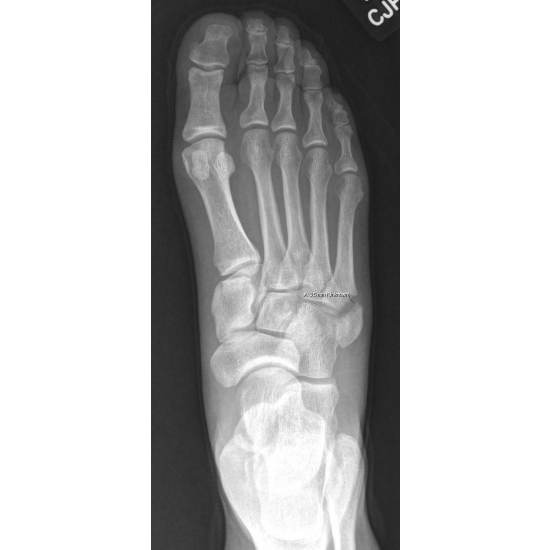

A 48-year-old-female runner complained of right lateral foot pain after running the bases at a softball game. She inverted her ankle on second base and felt a crack, but kept playing afterwards. She initially self-treated with a walking boot, but later went to the sports medicine clinic and was diagnosed with a right fifth metatarsal fracture. Case Photo #1 Case Photo #2